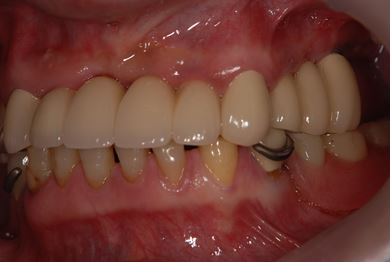

インプラントの症例写真 IMPLANT

骨再生スピードインプラント治療+セラミック治療

| 性別/年齢 | 男性 / 53歳 | ||||||||||||||||||||||||||||||||

| 主訴 | インプラント治療の相談。 | ||||||||||||||||||||||||||||||||

| 治療方針 | 上前歯部は、抜歯と同時にインプラントを埋入し、治療期間を短縮する。左上奥は、ソケットリフトにて上顎洞を拳上し、インプラント治療を可能にする。 | ||||||||||||||||||||||||||||||||

| 治療内容 | インプラント4本(ソケットリフト・抜歯即日)、テンポラリーインプラント2本、メタルボンドクラウン9本 | ||||||||||||||||||||||||||||||||

| 総治療費 | 2,025,975円 | ||||||||||||||||||||||||||||||||

| 治療期間 | 1年9ヶ月 |